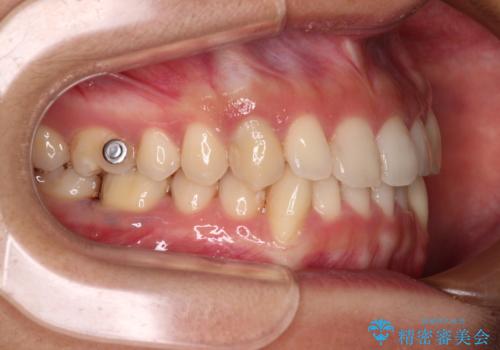

- 下顎の八重歯を気にして来院された患者様です。

マウスピース矯正でもワイヤー矯正でも対応可能であり、マウスピースによる治療を希望されたため、インビザラインを用いることとしました。

下顎前歯にデコボコが集中していたため、顎間ゴムによる後方移動とIPR(歯と歯の間を削ること)により歯列を整えることとしました。

しっかりとマウスピースを装着してくださったおかげで、スムーズに治療を終えることができました。

矯正治療途中で右下奥歯の虫歯治療を近医で行ったようで、既に神経が失活していたと合わせて矯正治療後に補綴治療を行う予定です。